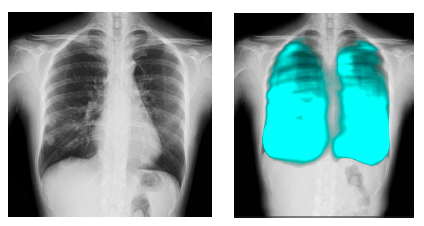

コニカミノルタのX線動態解析技術/イメージングAI技術と,FPTの高度なAI技術を活用し,呼吸器疾患の診断支援,医療レポートの自動生成など新しい診断技術の確立を目指す。コニカミノルタ独自の「X線動態解析」は,世界で300件以上の特許を取得しており,既に400台以上の販売実績がある。ベトナムの医療イノベーションとデジタル変革による呼吸器疾患対策を推進することで,国民の健康と医療従事者の負担軽減に貢献する。

簡易かつ高度なX線動態解析画像を用いた呼吸器疾患に関する医療指標の開発と,AI診断支援ツールの開発による呼吸器疾患の早期診断機会創出

コニカミノルタはデジタルX線動態撮影および動態解析を,新しい”動きの診断”を提供するソリューションとして展開している。この同社独自の技術「X線動態解析」を搭載したシステムとして,一般X線撮影装置を用いて動画を撮影できるデジタルX線動態撮影システムを開発・提供しており,既に国内外の医療機関で導入実績がある。